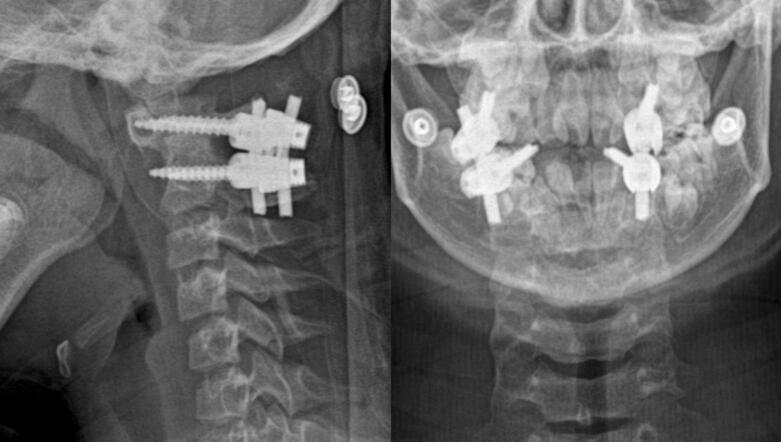

We present two cases of Os odontoideum accompanied by Down syndrome. Both patients were hospitalized due to progressive tetraparesis after falls several months prior. Upon examination, the patients exhibited myelopathy and were unable to walk or stand. MRI revealed spinal stenosis at the C1-C2 level due to atlantoaxial dislocation. C1-C2 fixation using Harms' technique was performed in both cases. One case experienced a complication involving instrument failure, necessitating revision surgery.

我们报告两例伴有唐氏综合征的齿突缺如病例。两名患者均因数月前跌倒后进行性四肢轻瘫入院。检查时,患者表现出脊髓病,无法行走或站立。MRI显示由于寰枢椎脱位,C1-C2水平存在椎管狭窄。两例均采用哈姆斯(Harms)技术进行C1-C2固定。其中一例出现器械故障并发症,需要进行翻修手术。